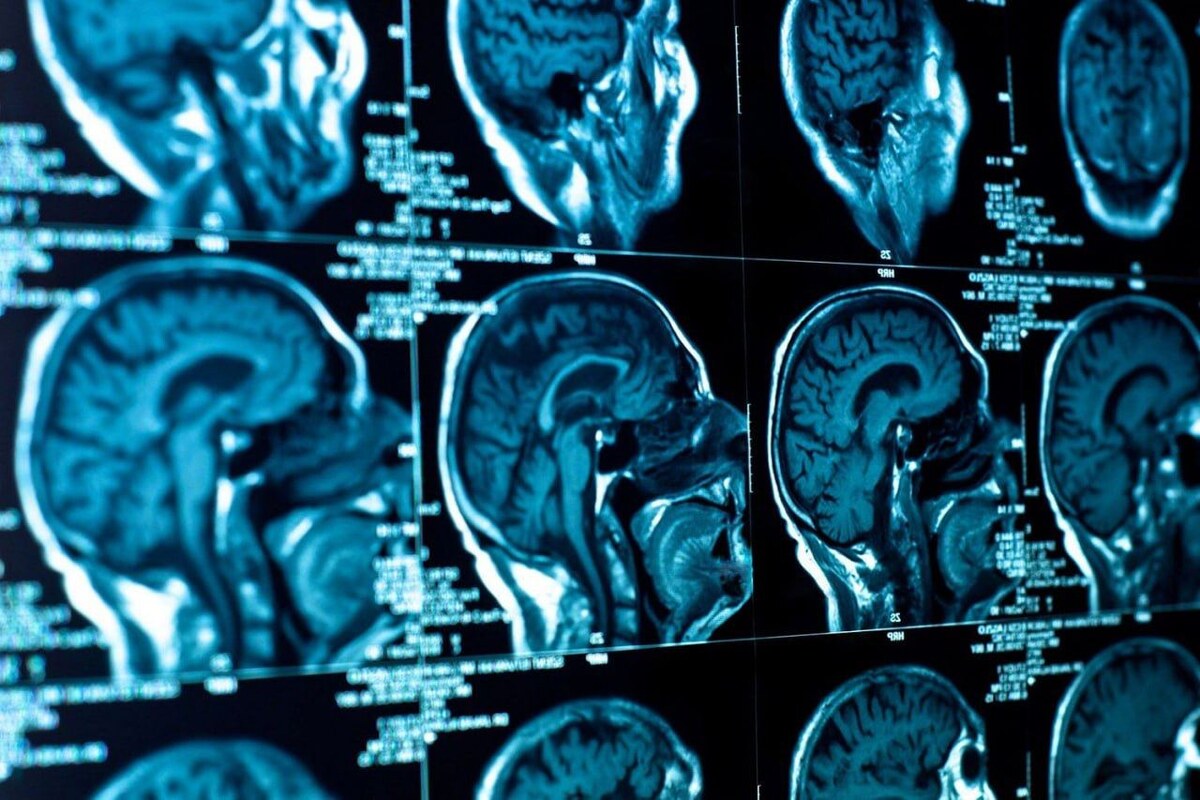

При этом 70% выручки обеспечили российские заказчики, около 25% – международные. NtechLab запустила долгосрочные стратегические проекты с рядом российских регионов – в частности, с Москвой, Нижегородской областью, подписала соглашения с Республиками Татарстан и Чувашия, Новосибирской и Саратовской областями, Краснодарским краем. Кроме того, компания существенно расширила линейку и вышла на рынок медицинских технологий, выпустив продукт для диагностики инсультов NtechMed CT Brain – решение уже используется врачами в московских клиниках. В высокой степени готовности находятся продукты для определения опухолей головного мозга и ранних признаков болезни Альцгеймера по КТ-снимкам.